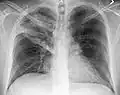

Normal AP CXR

AP CXR showing left lower lobe pneumonia associated with a small left sided pleural effusion -

AP CXR showing right lower lobe pneumonia -

AP CXR showing pneumonia of the lingula of the left lung -

Right upper lobe pneumonia as marked by the circle. -

Left upper lobe pneumonia with a small pleural effusion.

Right lower lobe pneumonia as seen on a lateral CXR